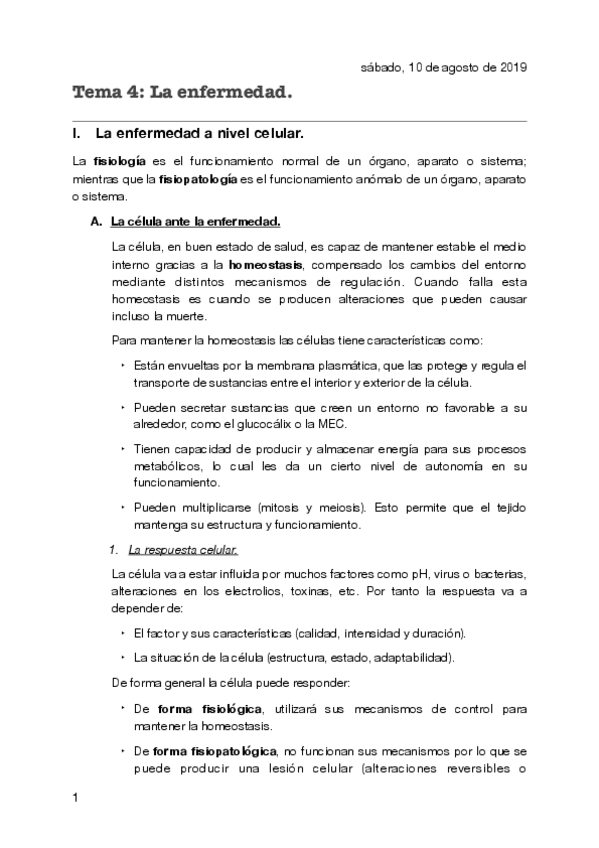

He publicado nuevos apuntes de Fisiopatología general: Tema-4-La-enfermedad.pdf